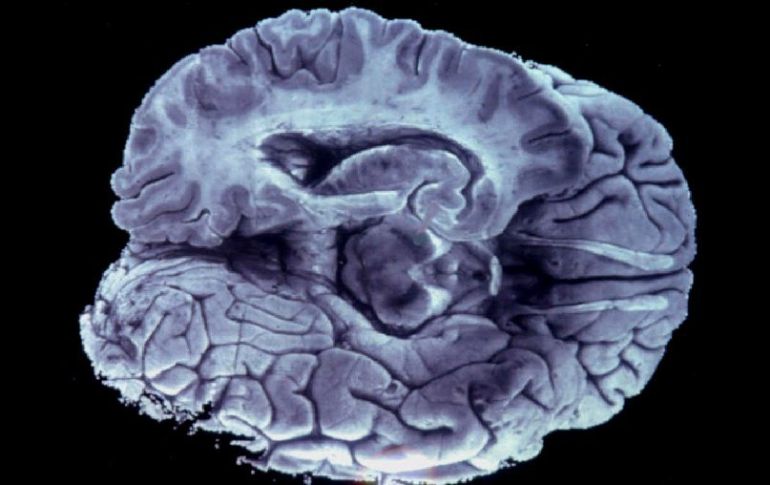

Tecnología | El área de Wernicke está delante de la corteza auditiva y no detrás, como se creía La parte del cerebro que procesa el habla no está donde se creía El área de Wernicke está delante de la corteza auditiva y no detrás, como se creía Por: AFP 30 de enero de 2012 - 13:40 hs Basaron investigación en 115 estudios que investigaron percepción del habla con imágenes de resonancia magnética o tomografías. EFE / WASHINGTON, ESTADOS UNIDOS (30/ENE/2012).- La parte del cerebro humano que procesa el habla se encuentra localizada en una sección diferente a la que se creía, de acuerdo con un estudio estadounidense publicado este lunes, por lo que los científicos señalaron la necesidad de actualizar los textos médicos. Durante mucho tiempo, se creyó que el área de Wernicke, que lleva el nombre del neurólogo alemán que la definió a finales de los años 1,800, se localizaba en la parte posterior de la corteza cerebral, detrás de la corteza auditiva, que procesa los sonidos. Pero un estudio científico del Centro Médico de la Universidad de Georgetown, en Washington, que tomó en cuenta más de 100 resonancias magnéticas, mostró que el área de Wernicke está tres centímetros más cerca de la parte frontal del cerebro y que se encuentra delante de la corteza auditiva, y no detrás como se creía. "Los libros de texto deben ser actualizados", dijo el profesor de neurociencias Josef Rauschecker, principal autor del estudio, que fue publicado en la revista Proceedings of the National Academy of Sciences. Rauschecker y sus colegas basaron su investigación en 115 estudios previos que investigaron la percepción del habla y usaron ya sea imágenes de resonancia magnética (IMR) o tomografías por emisión de positrones (PET por su sigla en inglés). Un análisis de las imágenes cerebrales del estudio arrojó la nueva localización del el área de Wernicke, dando una nueva perspectiva para tratar a los pacientes que sufren de daño cerebral o embolia. "Si un paciente no puede hablar o entender el lenguaje, ahora tenemos una buena pista sobre el lugar en el que el daño se produjo", dijo Rauschecker. El descubrimiento aporta además inquietantes interrogantes sobre los origenes del lenguaje de los humanos y los primates, cuya zona cerebral de procesamiento del lenguaje se sitúa en la misma zona que la nueva área de Wernicke de los humanos. "Estos hallazgos sugieren que la arquitectura y el procesamiento entre las dos especies es más similar de lo que la gente creía", dijo Rauschecker. Otro de los principales autores del estudio, Iain DeWitt, un candidato a doctorado del Programa Interdisciplinario de Neurociencias de la Universidad de Georgetown, dijo que el estudio confirma lo que otros han hallado desde que fue posible realizar imágenes cerebrales a principios de los años 90. "La mayoría de los expertos en imágenes cerebrales se rehusaban a contradecir un siglo de conocimientos con base en lo que entonces era una metodología relativamente nueva", dijo. "El objetivo de nuestro estudio es impulsar la reconciliación entre la información (disponible) y la teoría", concluyó. Temas Ciencia Estudios científicos Cerebro Lee También Nobel de Química premia el desarrollo de estructuras metal-orgánicas Nobel de Física para Clarke, Devoret y Martinis por descubrimiento sobre fenómenos cuánticos Nobel de Medicina premia investigación sobre el control del sistema inmunitario ¿Qué desencadena el párkinson en el cerebro? Científicos lo explican Recibe las últimas noticias en tu e-mail Todo lo que necesitas saber para comenzar tu día Registrarse implica aceptar los Términos y Condiciones